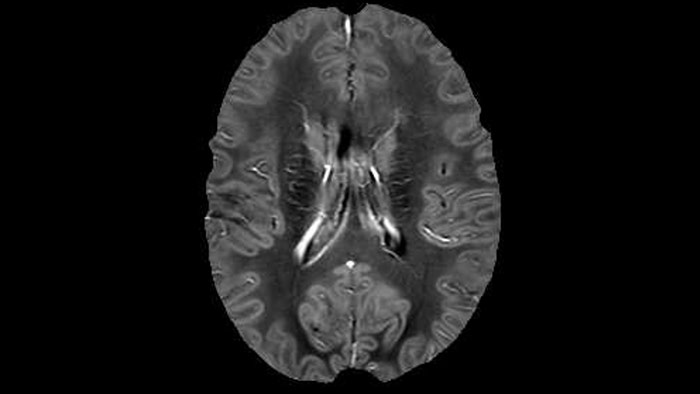

Dr. Rauscher says, “For MWI we perform 3D T2 with 32 or more echoes. This used to take a long time, but with Compressed SENSE we can decrease this to ten minutes for the whole head. Because of the large field of view (FOV) on the readout direction, we even get information from the brainstem, which we previously missed when we were using the GRASE approach. Having the whole head scan is nice because it has spatial resolution, orientation and FOV that are comparable to the standard 3D clinical MS scans, including the FLAIR and 3D T2, and a 3D T1 for brain volume.”

T1 - weighted

Myelin water imaging - T1 weighted

Myelin water imaging (echo 1)

Myelin water imaging with SENSE

Myelin water imaging with Compressed SENSE

With SENSE

With Compressed SENSE

Acquired resolution:

1 x 2 x 5 mm3

1.5 x 2 x 3 mm3

Number of echoes:

32 or 48

56

Echo spacing:

10 ms or 8 ms

7 ms

T1 - Weighted, Myelin Water Fraction Superimposed

MWI Spinal cord coverage

Spinal cord coverage

MWI Smaller, more isotropic voxels

Smaller, more isotropic voxels

MWI Excellent detail in quantitative maps

Excellent detail in quantitative maps

Images courtesy of Adam Dvorak, Department of Physics and Astronomy, University of British Columbia

20%

Myelin water fraction

0%